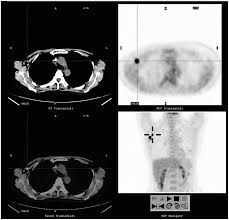

Pet/ct scans work well for breast, lung, colon and other. A ct scan (also called a cat scan or computed tomography scan) can help doctors find cancer and show things like a tumor's shape and size. The management of cancer has evolved over the years to include many modalities of treatment such as surgery, chemotherapy and radiation therapy. This test may reveal whether breast cancer has spread to the bone. A computed tomography (ct or cat) scan allows doctors to see inside your body. Positron emission tomography (pet) scans detect early signs of cancer, heart disease and brain disorders. Pet/ct scans provide significantly more information than ct scans, and are far more reliable when diagnosing cancer. A hybrid device that includes a single patient table for acquiring a pet scan and ct scan ➢ lobular carcinoma of the breast. The pet scanner detects signals that are given off from the tracer. Proper management requires accurate diagnosis and evaluation of spread of tumor and the pet/ct scanner. Pet scans, short for positron emission tomography, can detect areas of cancer by obtaining images of the body's cells as they work. Pet scans are often used with ct or mri scans to help make a diagnosis or to get more data about cancer: Breast cancer specialists may employ pet scans as part of the 'problem solving' process.

Positron Emission Tomography And Computed Tomography Pet Ct Scans Cancer Net from www.cancer.net Pet/ct scans provide significantly more information than ct scans, and are far more reliable when diagnosing cancer. 25.8) with a history of breast cancer and merkel cell cancer of the chin. Each has its own strengths. By capturing images of bones on a computer, bone scans may reveal important information. Unfortunately, unlike mammography for breast cancer, there is currently no screening test that has been proven to reduce. Ct scans can detect cancer at a very small size. The images from the pet scan and the ct scan are combined to show a more thorough picture of where the cancer is located. It usually takes between 30 and 60 minutes.

Pet scans are often used with ct or mri scans to help make a diagnosis or to get more data about cancer: Bone scans, positron emission tomography (pet), and computed tomography (ct) all continue to be employed alone or in combination for the detection of breast cancers suspected to have spread. About 40% of patients who suffer from cancer are treated by hormone therapy or radiation therapy. Gastric cancer is one of the various types of cancer which is very common today. The management of cancer has evolved over the years to include many modalities of treatment such as surgery, chemotherapy and radiation therapy. Find out how you have it. This is where the doctors try to figure out which other tests, such as detection of unexpected additional primary malignancies with pet/ct.j nucl med. Each has its own strengths. Prostate pet/ct scans can detect cancer earlier than either ct scans alone or mri scans. In some cases, physicians use all three imaging techniques. One example is a combined pet and ct scan (known as pet/ct), available in some centers. This provides a series of images from many different angles. Positron emission tomography (pet) scans detect early signs of cancer, heart disease and brain disorders.

Often, a ct scan is done at the same time. Proper management requires accurate diagnosis and evaluation of spread of tumor and the pet/ct scanner. Each has its own strengths. Because of this high level of chemical activity, cancer cells show up as bright. 38 in 33 patients, biopsy. Pet/ct scans work well for breast, lung, colon and other. Are they as reliable in detecting breast cancer as a regular mammogram? Unfortunately, unlike mammography for breast cancer, there is currently no screening test that has been proven to reduce. An injectable radioactive tracer detects diseased cells. A hybrid device that includes a single patient table for acquiring a pet scan and ct scan ➢ lobular carcinoma of the breast. Pet/ct scans provide significantly more information than ct scans, and are far more reliable when diagnosing cancer. Find out how you have it. While it might seem obvious to assume that finding small tumors reduces one's likelihood of dying from lung cancer, this is incorrect.